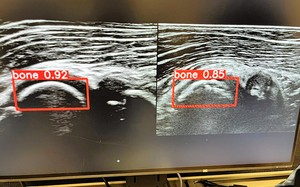

Study: AI system finds baseball elbow injuries in the early stages

June 25, 2024